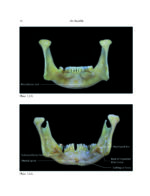

THE MANDIBLE: An Atlas Osteological and Radiological Anatomy 2022

کتاب افست و اطلس رنگی و ارزشمند”THE MANDIBLE: An Atlas Osteological and Radiological Anatomy 2022 ” ویرایش اول